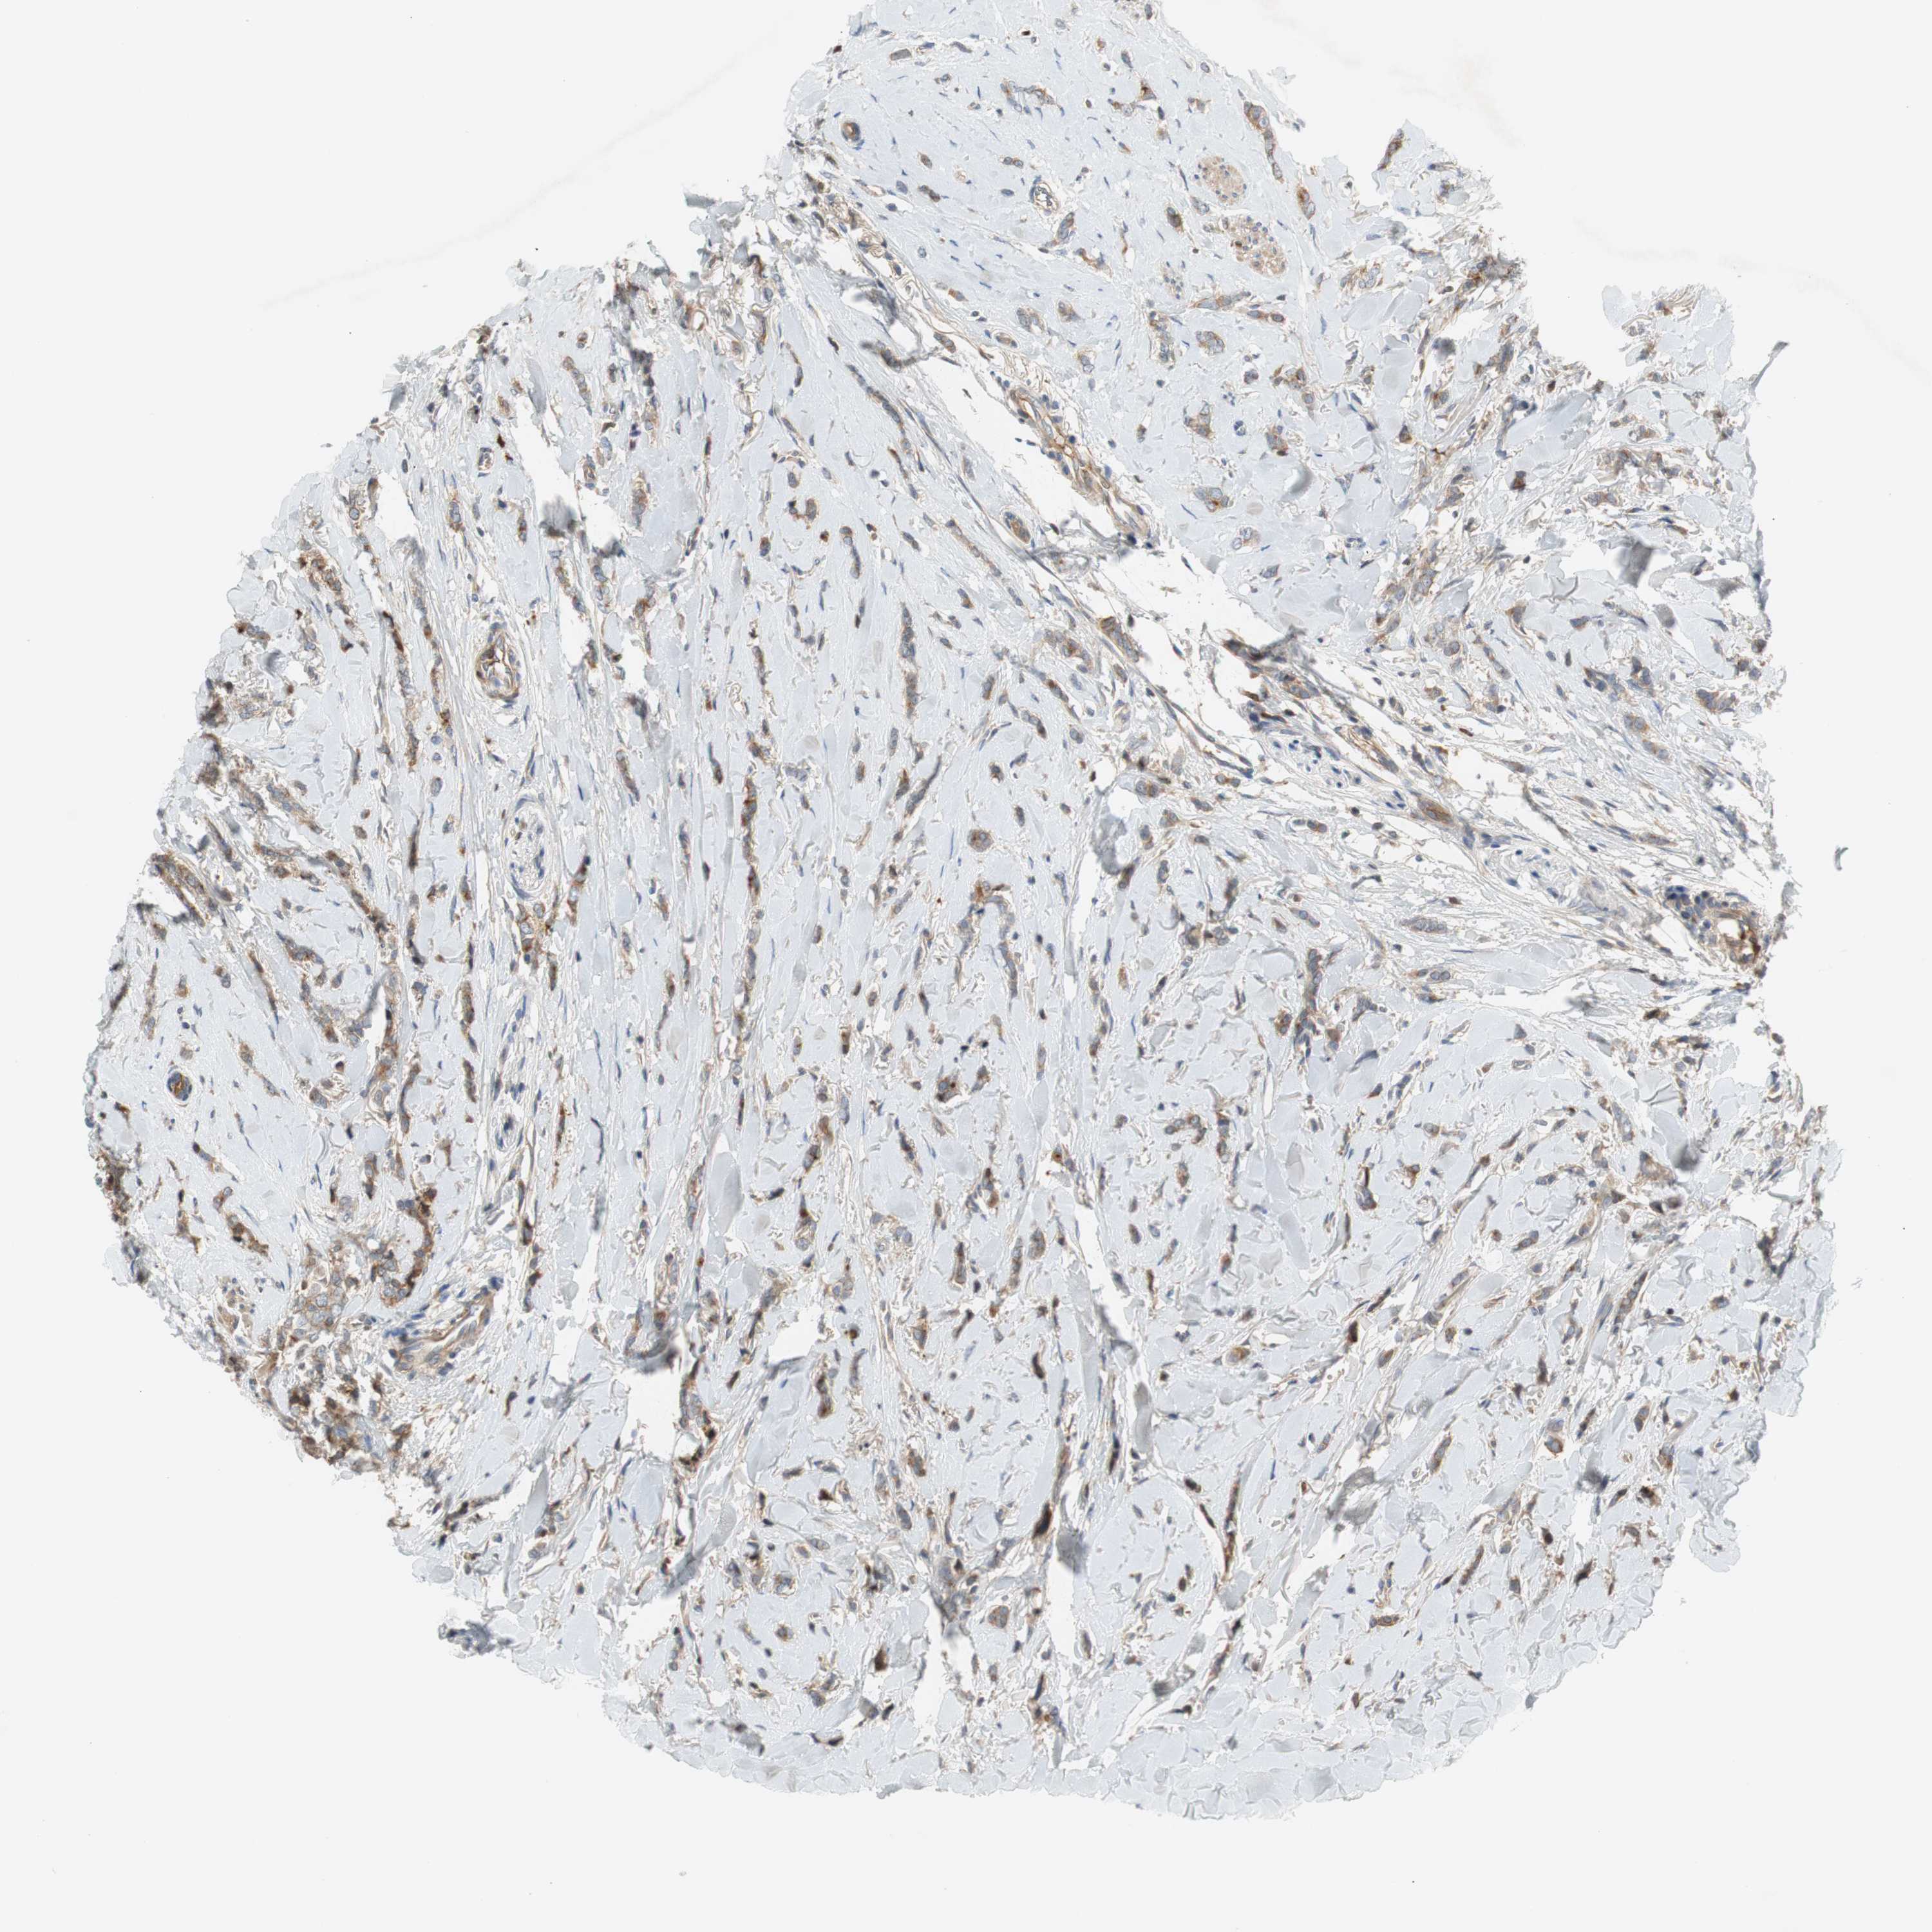

BRCA TCGA BRCA VALIDATION PROTEIN EXPRESSION

ANTIBODIES

AND

VALIDATION